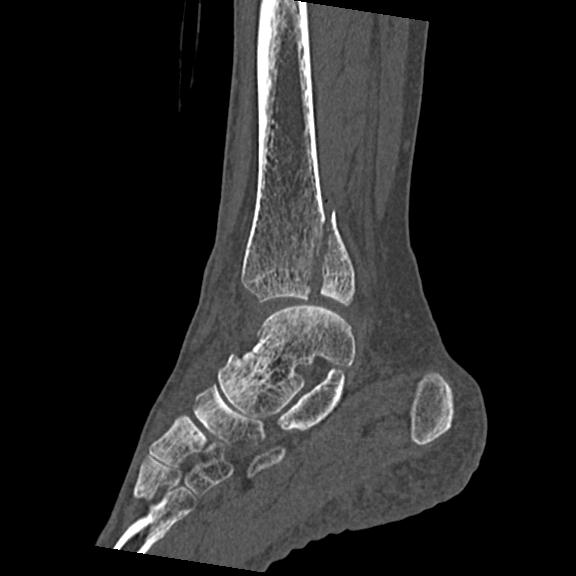

102755 1/4 2R 1/15 2R 右足関節 68歳女性 右三果脱臼骨折

56476 8/28 4R 1/21 2R 左足関節 デジカメ写真 72歳女性 右足関節AS